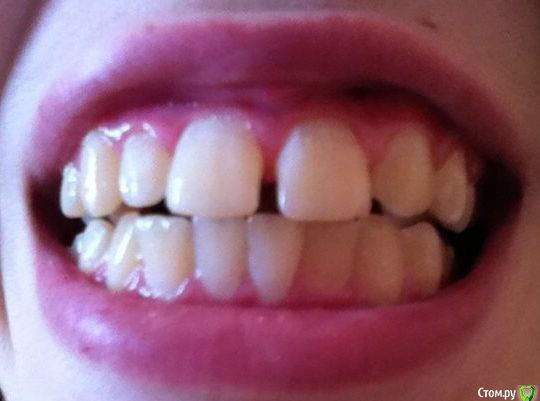

Illina Опубликовано 2 августа, 2019 Поделиться Опубликовано 2 августа, 2019 Добрый день! Девушке 18 лет.Нет левой верхней двойки, из-за чего между зубами верхними щели.Не улыбается прилюдно(Консультировались лет в 16 у ортодонта, сказал ждать 18 лет. Читала про 2 тактики - 1) смещение зубов с целью убрать щели и 2) имплантацию отсутствующей двойки. Цель самой девушки - избавиться от щели, то есть наверное 1 вариант бы устроил.Но будет ли результат постоянен? Не раздвинутся ли зубы после снятия брекетов опять?? Спасибо Ссылка на комментарий